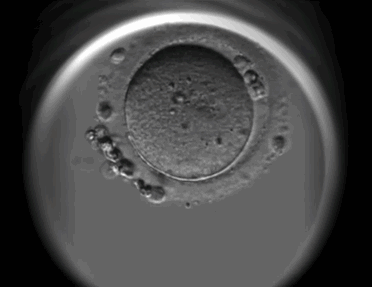

男性的生殖细胞最终形成装着“22条常染色体+X”或者“22+Y”的两种送货小车,而女性生殖细胞最终只能形成“22+X”这一种送货小车。

因此,当两辆小车相遇时(精卵结合),便形成了核型为46,XX以及46,XY的“染色体套装”,分别对应着女性和男性。

可以说,精卵相遇的这一刻就已经决定了孩子的性别。